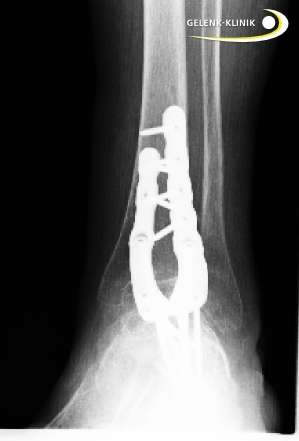

Arthrodese des Sprunggelenks statt Wechsel der Prothese

Versteifung des Sprunggelenks nach Revision einer Sprunggelenksprothese. Bei diesem Patienten erfolgte die Versteifung des oberen Sprunggelenks mit Hilfe einer Plattenosteosynthese. Die Platten werden von außen gegen das zu versteifende Gelenk geschraubt, um die Gelenkpartner in Position zu halten. © Gelenk-Klinik

Auch nach einer Prothesenversorgung kann die Versteifung des oberen Sprunggelenkes als Revisionsoperation eine Rolle spielen. Eine Sprunggelenksprothese kann aus mehreren Gründen versagen: Abnutzung, Fehlpositionierung oder ungenügende Herstellung einer prothesenverträglichen Sprunggelenksachse. Wenn die Sprunggelenksprothese nicht mehr funktioniert, besteht die Therapie der ersten Wahl natürlich Behebung in der der Ursachen für den Prothesenverschleiß und Prothesenwechsel. In manchen Fällen muss nach Ausbau der Prothese das Sprunggelenk versteift werden. Nach dem Versagen einer Sprunggelenkprothese müssen wir immer damit zurecht kommen, dass ein Teil der Knochensubstanz an Talus (Sprungbein), Tibia (Schienbein) und Fibula (Wadenbein) abgetragen wurde, um den erstmaligen Einbau der Prothese zu ermöglichen. Bei einer erneuten Prothesenverankerung steigt also die Wahrscheinlichkeit von Problemen bei der Verankerung. Dazu gehört beispielsweise eine Fraktur der Sprunggelenksgabel aus Mangel an verfügbarer Knochensubstanz. Scheint uns dieses Risiko nach Untersuchung der verfügbaren Knochensubstanz zu hoch, wählen wir eher die Versteifung als sichere Alternative zum Prothesenwechsel.